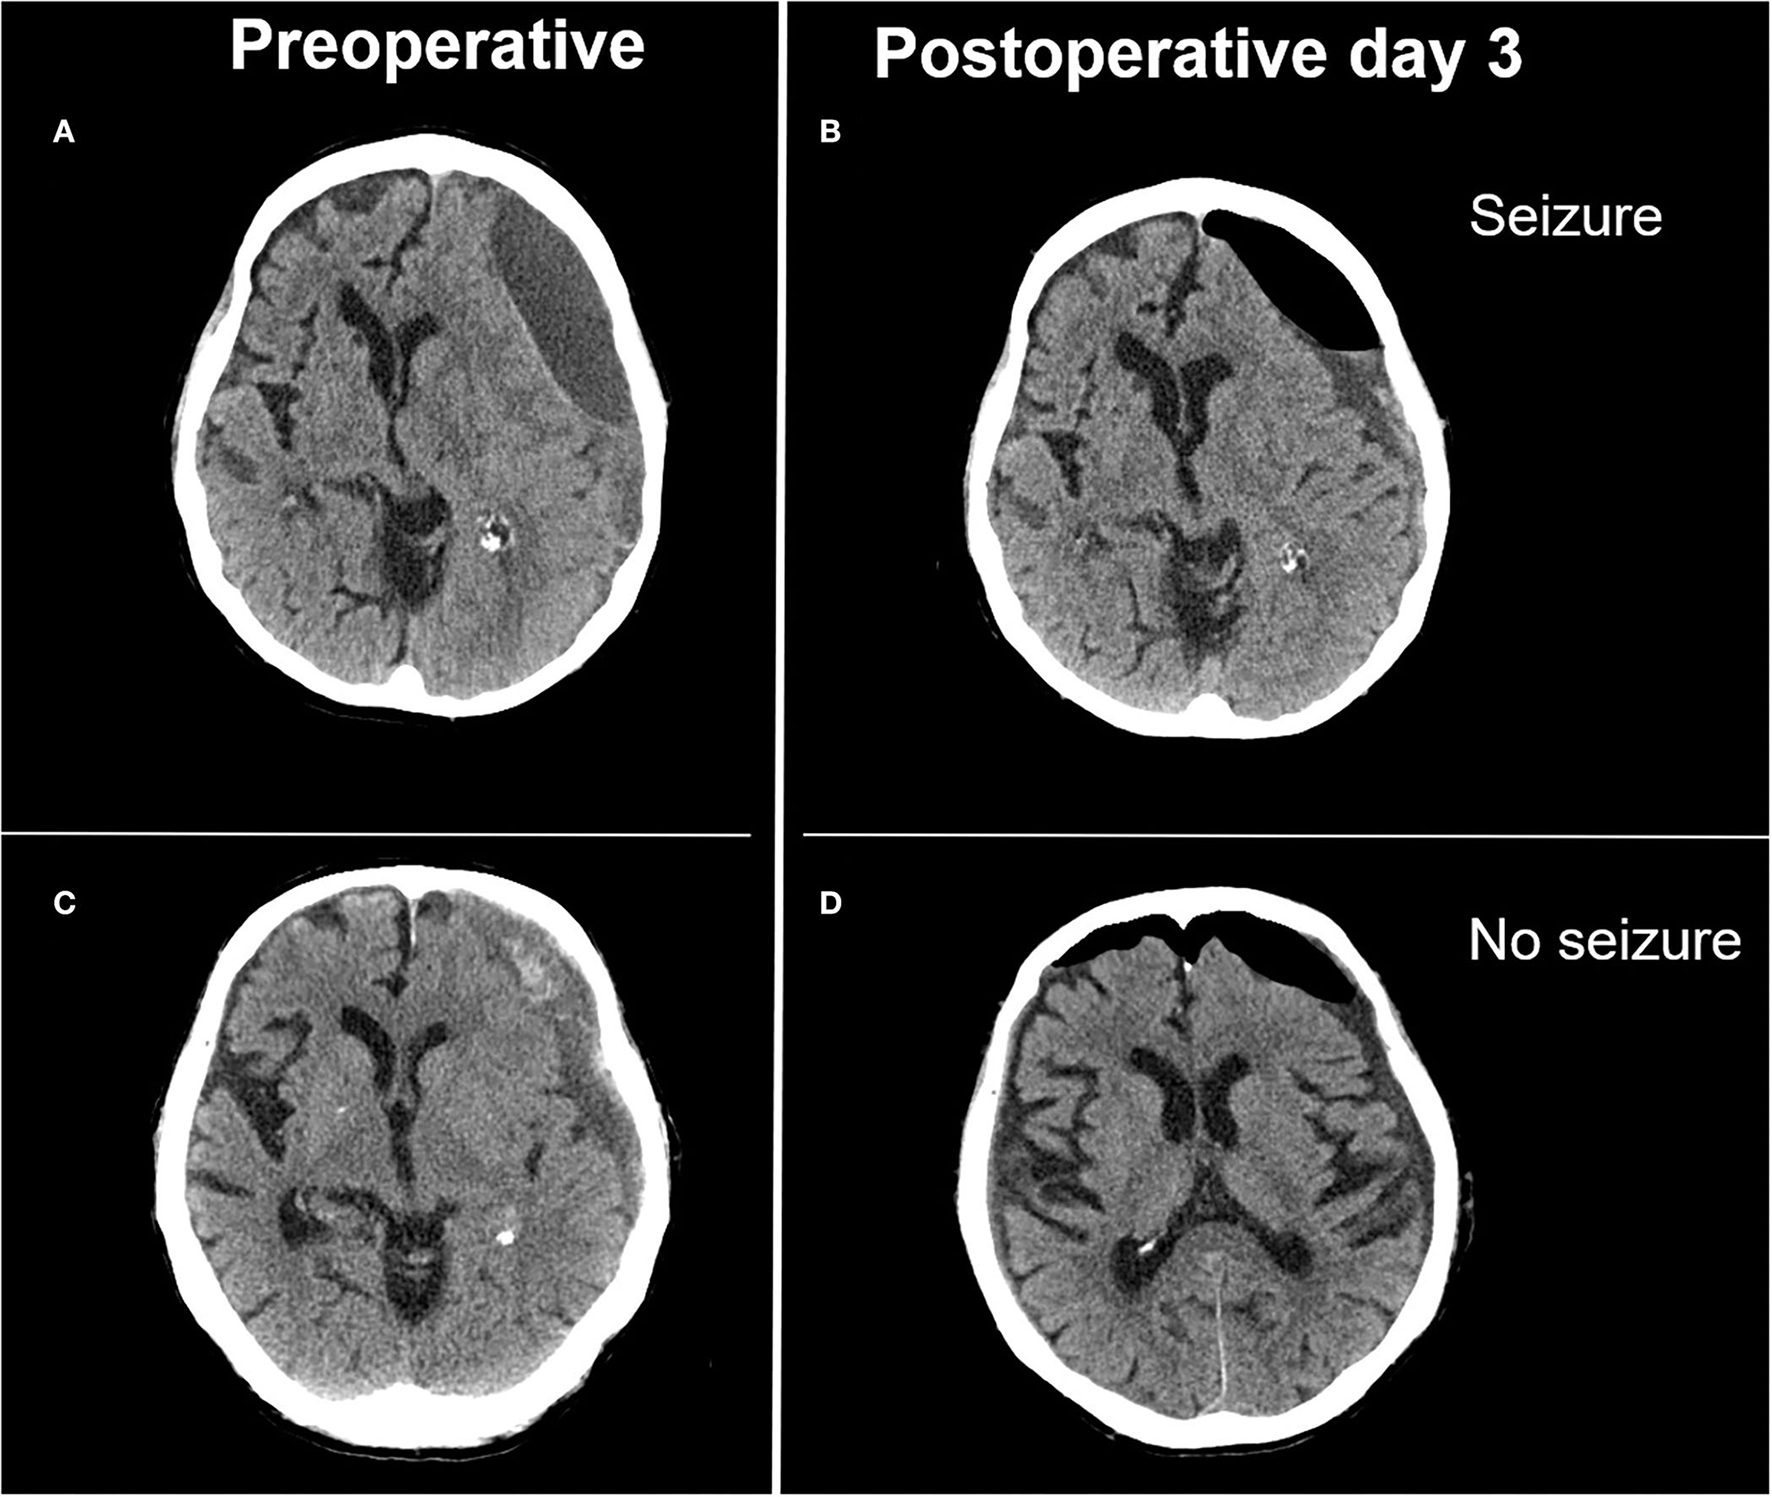

Seizures after treatment for chronic subdural hematoma considerably complicate hospital stays and can even necessitate intensive care observation and treatment. In this consecutive 4 years series of patients surgically treated for cSDH, the observed rate of epileptic seizures of 15.5% lies at the upper margins of incidences previously described in a similar series (9, 17). Only postoperative depressed brain volume proved independently associated with seizure occurrence (Figure 2). An epileptic seizure was, alongside initial clinical state, a significant predictor of clinical outcome and increased the rate of unfavorable outcome as measured via the Glasgow outcome scale.

Figure 2

Illustrative case of extensive depressed brain volume leading to postoperative seizure and adequate postoperative brain expansion not associated with postoperative seizure. (A) Preoperative image of a laminar type hematoma demonstrating limited brain re-expansion (B) after hematoma evacuation. Patient presented with focal seizures on postoperative day 3. (C) Preoperative image of a trabecular type hematoma with adequate brain re-expansion (D) and no postoperative seizure activity.